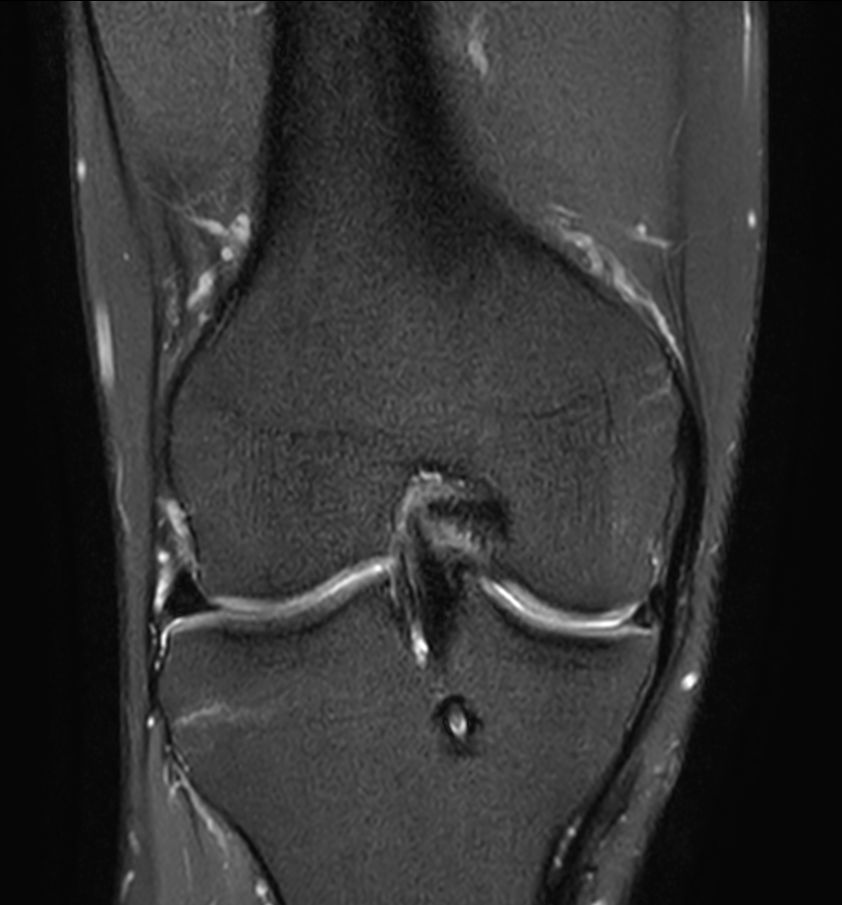

Coronal PDw SPAIRCompressed SENSE